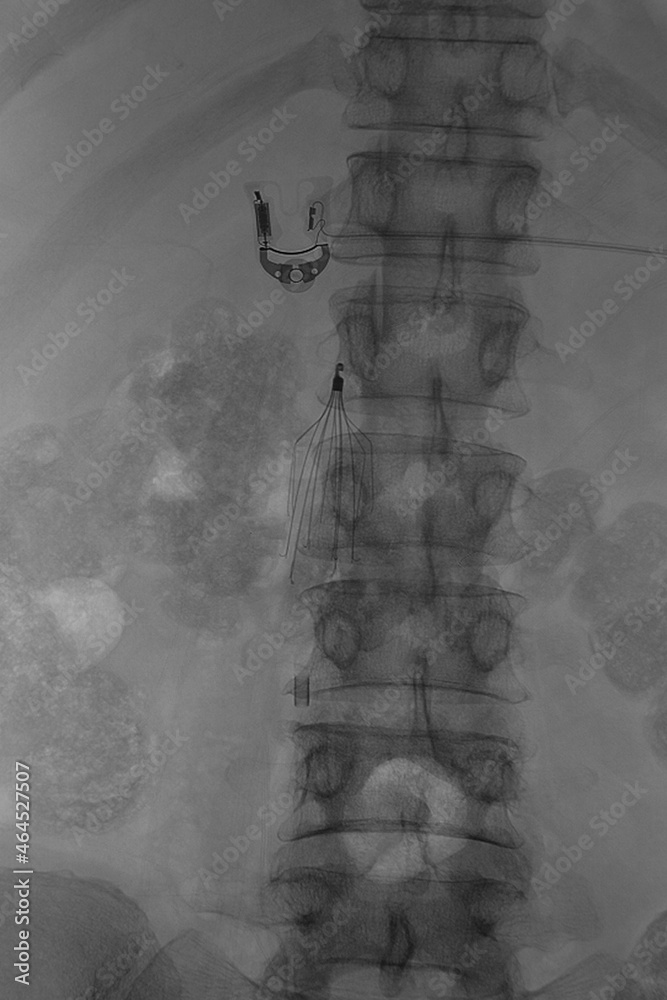

Xray was perform inferior vena cava (IVC) filter placement, IVC filter Ivc Filter On X Ray For example, certain types of ivc filters have been found to. The heart then pumps the. The ivc returns blood from your lower body to your heart. Inferior vena cava (ivc) filters are placed in patients who have a history of or are at risk of developing blood clots in the legs, including. The procedure will take about 30. Ivc. Ivc Filter On X Ray.